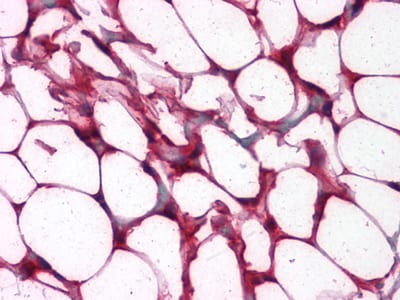

Immunohistochemical analysis of paraffin-embedded human Colon, Adipocytes tissues using anti-PPARa mouse mAb